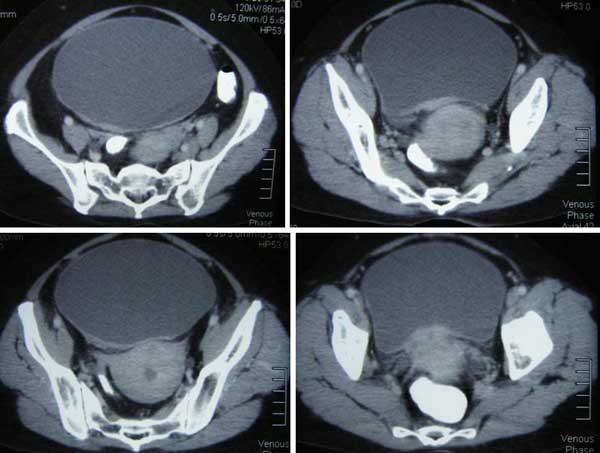

CT report dated 27 April 2012 indicated: Multiple simple renal cortical cysts seen bilaterally. Moderate right hydronephrosis and hydroureter as well as mild left hydronephrosis and hydroureter seen. Grossly distended urinary bladder. Fuzzy, irregular cervical edges noted. Impression: 1. Grossly distended urinary bladder with bilateral urinary tracts ? back pressure. 2. Fuzzy, irregular cervical edges. Suggest gynaecological assessment.